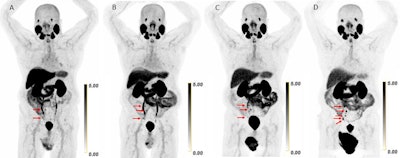

Scans in a 73-year-old man with biochemically recurrent prostate cancer (prostate-specific antigen level of 0.5 ng/mL) who underwent PET/CT with 9.4 mCi of F-18 piflufolastat and a second PET/CT examination with 8.1 mCi of copper 61-NODAGA (1,4,7-triazacyclononane,1-glutaric acid-4,7-acetic acid)–prostate-specific membrane antigen for imaging and therapy (Cu-61 PSMA I&T) 24 days apart, with no intervening therapy. Maximum intensity projection (MIP) images obtained (A) 1 hour after F-18 piflufolastat administration and (B) 1, (C) 2, and (D) 4 hours after Cu-61 PSMA I&T administration are shown. Physiologic uptake is seen in the lacrimal glands, salivary glands, liver, spleen, kidneys, ureters, and bladder. Pathologic uptake in pelvic nodal metastases is labeled with arrows. The F-18 piflufolastat PET/CT MIP image reveals two avid pelvic nodal metastases (arrows). Cu-61 PSMA I&T PET/CT scans demonstrate three avid pelvic nodal metastases on 1-hour and 2-hour images (arrows); five avid pelvic nodal metastases were suspected on the 4-hour image (arrows).RSNA